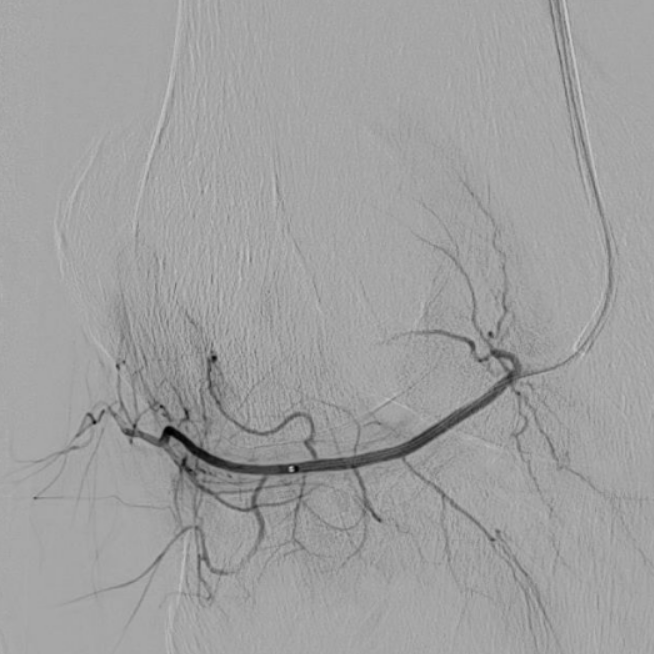

case of the day - 09.02.2026

Kniegelenk

Hier sehen Sie die Bilder vor und nach der Behandlung bei chronischen Kniegelenksbeschwerden. Sehr deutlich ist die geringere Kontrastmittelaufnahme nach Behandlung als Hinweis der verringerten Durchblutung der entzündeten Bereiche zu sehen.

Arteria genicularis inferior lateralis - vor Behandlung

Arteria genicularis inferior lateralis - nach Behandlung